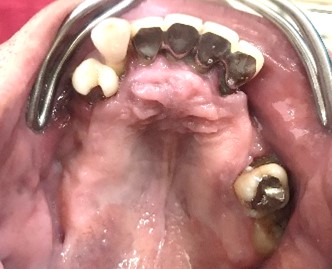

Before

赤丸は抜歯しました。上4本、下3本

After

【義歯を装着したところ】

【義歯を外したところ】